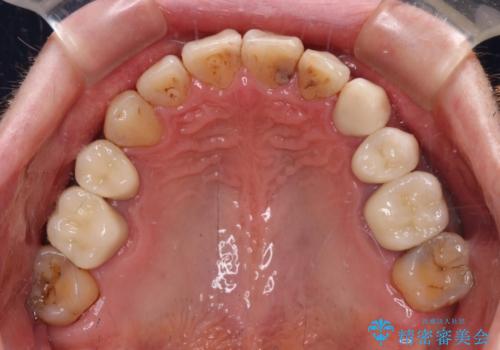

- むし歯による奥歯の痛みを気にして来院された患者様です。

神経にまでむし歯の及んでいる歯や、既に根管治療がされている歯に痛みがあったため、まずは根管治療を行うこととしました。

その後、以前行った抜歯矯正の後戻りをインビザライン・ライトにより改善し、むし歯や銀歯はオールセラミッククラウンにて補綴治療することとしました。

痛みは速やかに引き、銀歯や黒く変色したむし歯がセラミッククラウンで自然な色合いに仕上がり、患者様には大変満足していただきました。